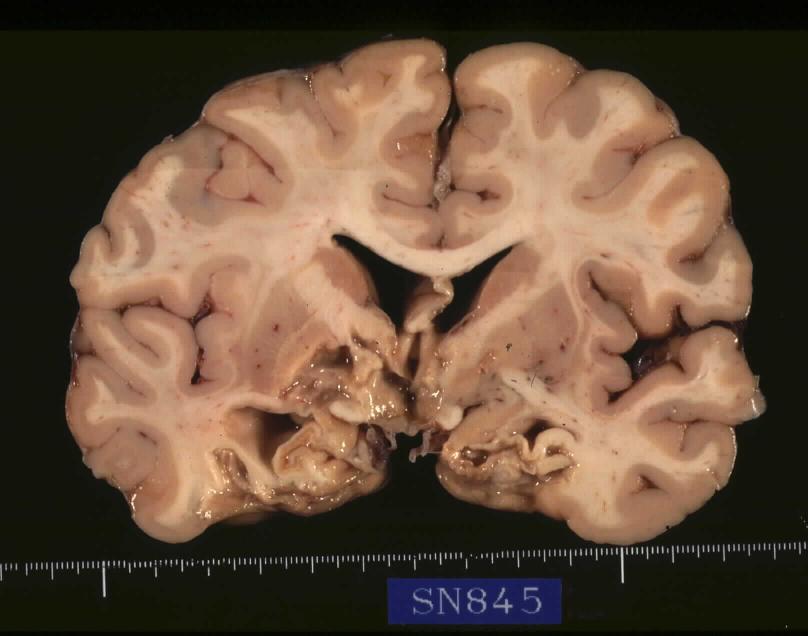

2. Brain, which weighs 1,265 gram inclusively, externally shows marked softening of both the inferior aspect of the cerebral hemispheres, particularly extensive anemic necrosis (infarct) of the inferomedial aspect of the bilateral temporal and occipital lobes. Sections in the coronal plane reveal extensive infarct involving the inferomedial surface of the occipital lobes including optic radiation, bilateral Ammon's horn, hypothalamus, and the left globus pallidus and internal capsule( [jpg.43KB]). Meynert nuclei are also involved. Only minimal arteriosclerosis is noted in the basilar and vertebral arteries. Substantia nigra macroscopically remains pigmented but in decreased intensity ( [jpg.56KB]). Microscopic examination reveals anemic necrosis with mobilization of foam macrophages, lymphocytic infiltrates, capillary proliferation and reactive astrocytosis at the margins of the infarct, which also is involving the substantia nigra and the mid pons slightly. A few Lewy bodies are identified in the pigmented nuclei of the substantia nigra ( [jpg.66KB]) and the nucleus tractus solitarii but none in the locus coeruleus, nucleus dorsalis n. vagi, neither in the cerebral cortex. The number of pigmented neuronal cells is decreased in substantia nigra ( [jpg.80KB]) and locus coeruleus ( [jpg.98KB]) compared with an age- and sex-matched control (SN 847, 70-year-old male), accompanied with scattered pigment-laden macrophages. Lipofuscin deposition in the cytoplasm of the neuronal cells is remarkable in the cerebral cortex. Neuronal cells of the reticular formation including those in the nuclei ambiguus of the medulla oblongata are intact. Pallor of the bilateral pyramids is noticed in the pons and medulla oblongata, moderate, the left side being more prominent, and in the upper cervical spinal cord, mild.